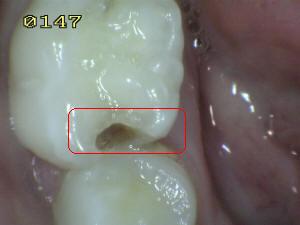

Sistema Internacional para la Detección y Evaluación de Caries (ICDAS)

¿Determine los códigos pertinentes a cada imagen?

Click en el hipervínculo: Para comparar el resultado de su diagnóstico